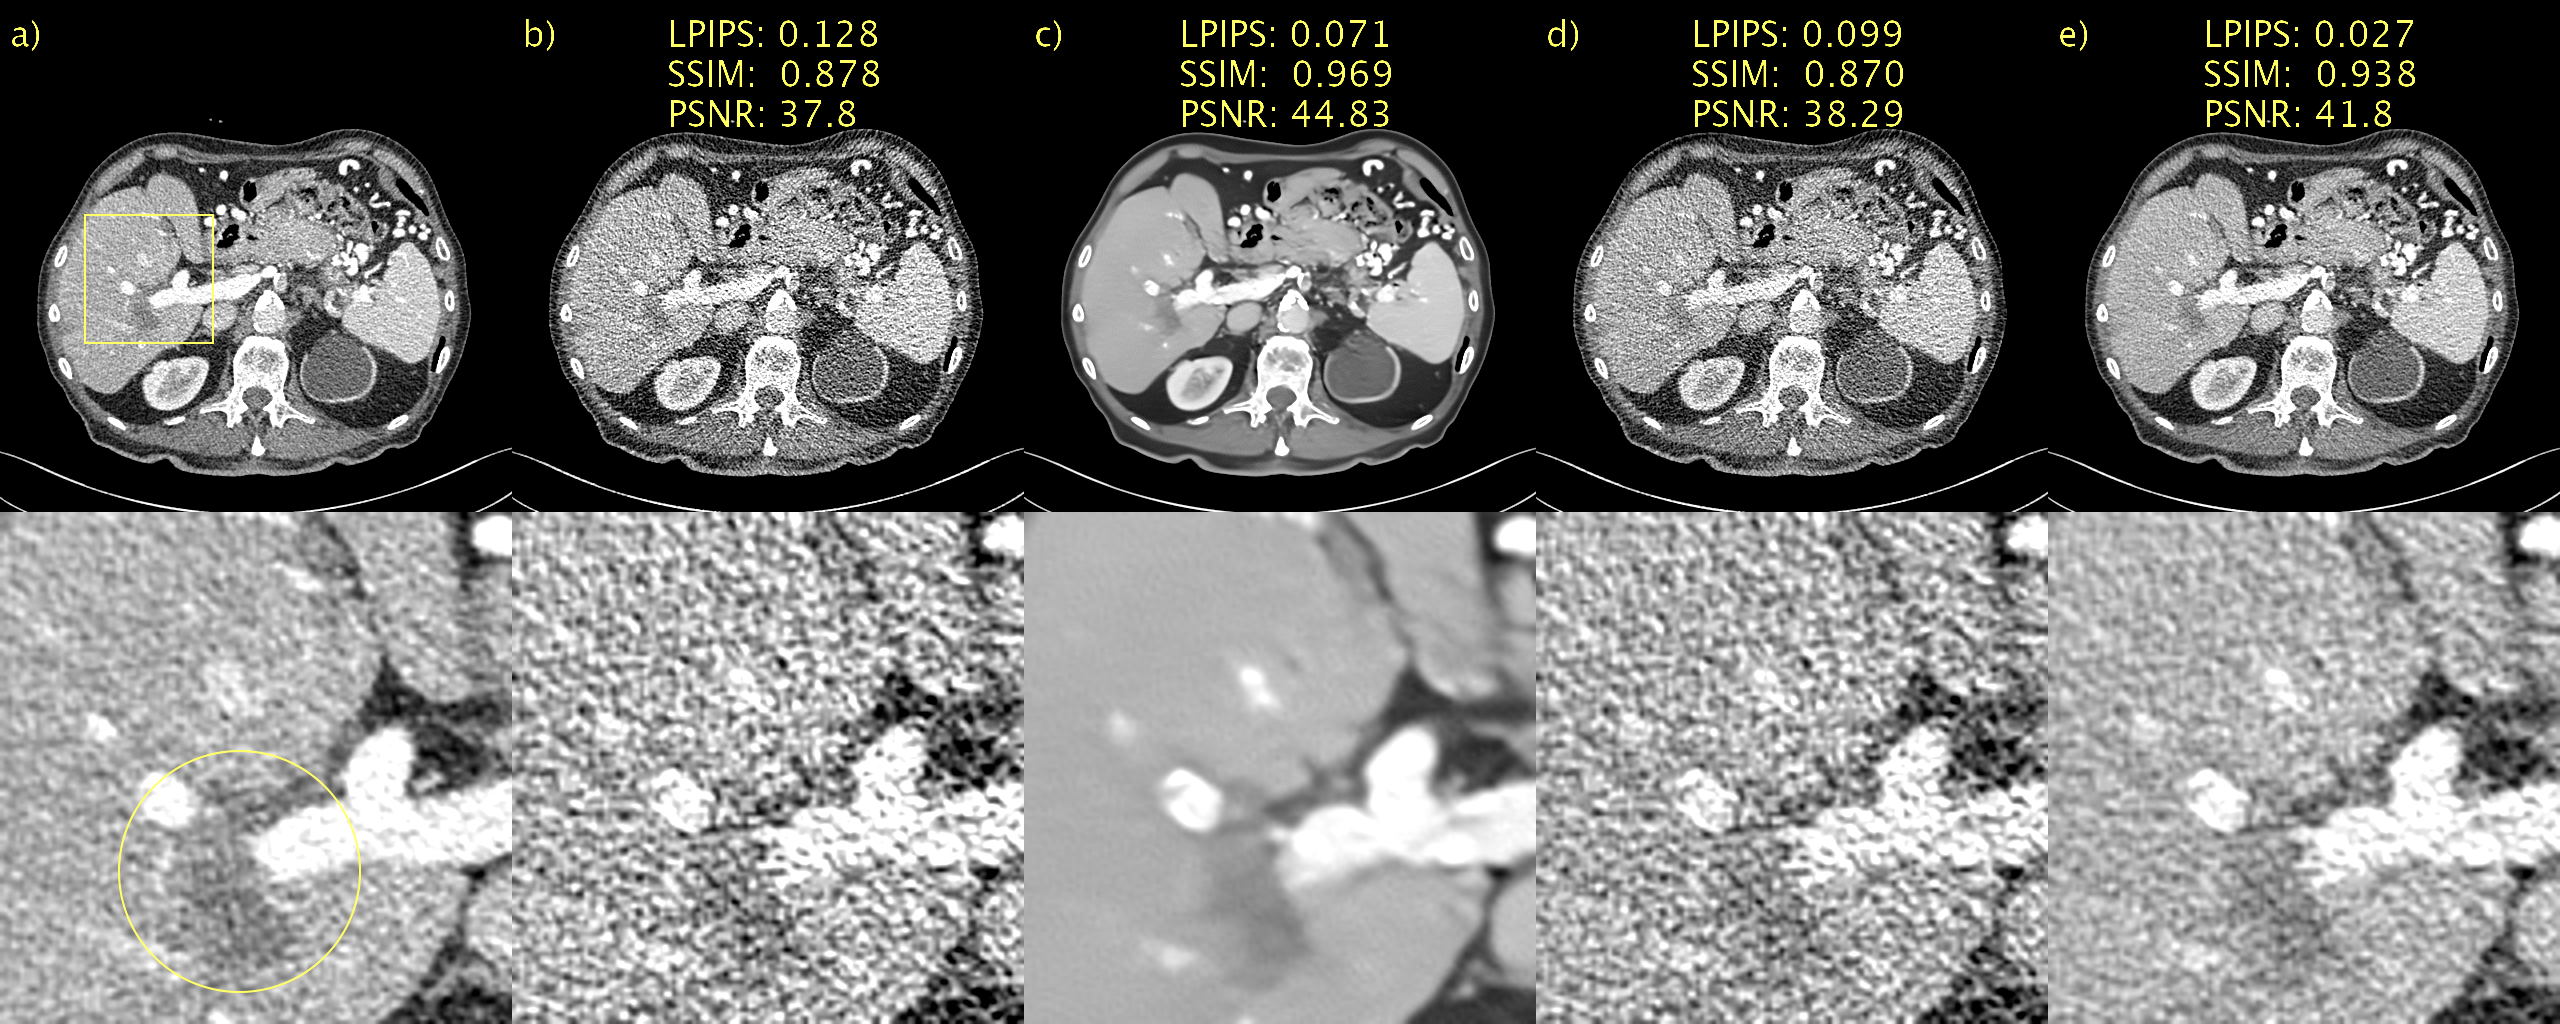

Results from an ablation study of the proposed sampler are available in Fig. 3. a) and b) show the NDCT and LDCT images for easy reference. In c) we hijack but omit regularization (τ=T1,w=1formulae-sequence𝜏𝑇1𝑤1\tau=T-1,w=1). The result is an image that has been very aggressively denoised. This is a direct consequence of the small T𝑇T and corresponding large step-size. This represents a further clean demonstration of how SSIM and PSNR fail to adequately penalize blurring as c) appears blurry to a human observed yet performs very well according to SSIM and PSNR. LPIPS, on the hand, penalizes this quite heavily. In d), we regularize but employ no hijacking (τ=0,w=0.5formulae-sequence𝜏0𝑤0.5\tau=0,w=0.5). In this case we start with an initial sample from the prior noise distribution. The amount of regularization in this setting seems excessive and we recover an image where 𝒚^𝒄.bold-^𝒚𝒄\bm{\hat{y}}\approx\bm{c}. Finally, in e) we employ hijacking and regularization (τ=T1,w=0.5formulae-sequence𝜏𝑇1𝑤0.5\tau=T-1,w=0.5), resulting in a very pleasing image where 𝒚^𝒚.bold-^𝒚𝒚\bm{\hat{y}}\approx\bm{y}. Consequently, there is a significant reduction (improvement) in LPIPS.

Refer to caption

Figure 3: Ablation study of regularizer used in our proposed sampler. a) NDCT, b) LDCT, c) only hijacking, d) only regularization, e) hijacking and regularization. Yellow circle added to emphasize lesion. 1 mm-slices. Window setting [-160,240] HU.